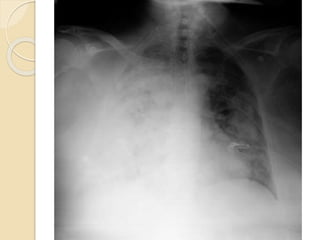

◦ Rx tórax

 PC: ◦ Analítica: Hb 7’8 g/dL  Leucocitos 15.300/mm3, neutrófilos 13.000./mm3  Creatinina 8’93 mg/dL  PCR 21’79 mg/L ◦ Test coombs directo: negativo ◦ EAB basal:  pH 7’34, pCO2 33, PO2 33, HCO3 17’8, láctico 1’3 ◦ Ag neumococo + legionella en orina: negativo ◦ Ag H1N1: negativo ◦ EKG: Rs. 66 lpm. Eje izquierda. ◦ Rx tórax